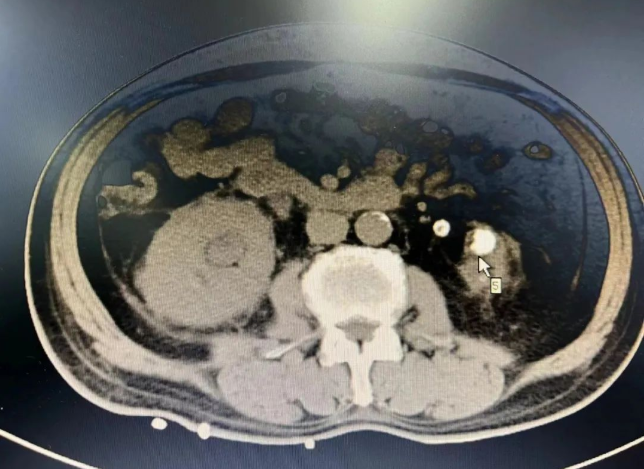

该患者73岁,在其他医疗机构诊断为尿毒症,给予透析治疗好转后返回昭通,继续血液透析2年余。于本年度上旬身体不适后转我院泌尿外科就诊,当时病情不容乐观。

泌尿外科副主任医师王国昆介绍道:“经检查患者病情后,首先考虑患者高龄并卧床休养很长时间,心肺功能差,左肾萎缩已无功能,长期透析治疗已经引发贫血、电解质紊乱等多种疾病,此外,右侧输尿管结石梗阻引起肾功能衰竭。”

经科室医护团队研判需及时开展手术,解除右侧输尿管结石梗阻,保护好仅有的右肾功能。但难题来了,患者只有一个右肾,行经皮肾镜碎石取石手术风险较大,万一术中或术后大出血无法止血,手术团队将面临切除右肾的风险,后果不堪设想。主管医师马青冬建议手术时需选择最佳穿刺点,轻柔操作避免大出血风险,术前做好充分备血准备。

团队达成一致意见,术前先经我院肾内科血液透析治疗改善肾功能,再由泌尿外科给予行右侧经皮肾盂钬激光碎石取石治疗,先保住右肾,再进行下步治疗。